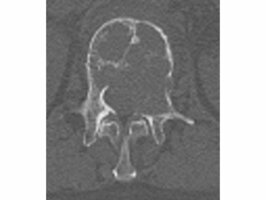

例えばCT写真(写真1)にあるように、腰骨(白い部分)には近くに脊髄があります。そのため、脊髄にできるだけ放射線が当たらないように、いろいろな方向からピンポイント照射することが可能になりました。その結果、転移も治癒できるようになってきているのが、(写真2)で示した最近の高精度放射線治療です。自分のがんが転移をしている場合、医師にこのような放射線治療ができないか確認してみてもよいでしょう。